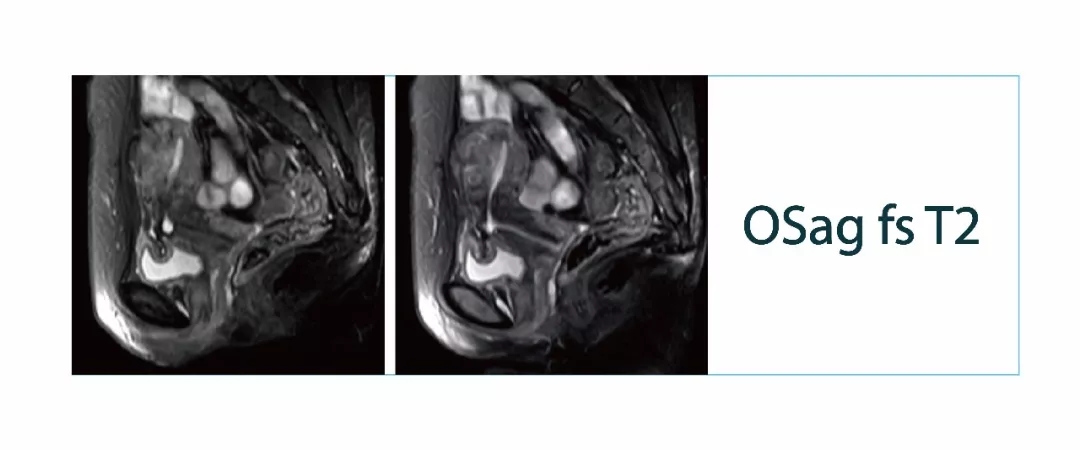

【朗润影像档案】20180309磁共振影像病例结果讨论